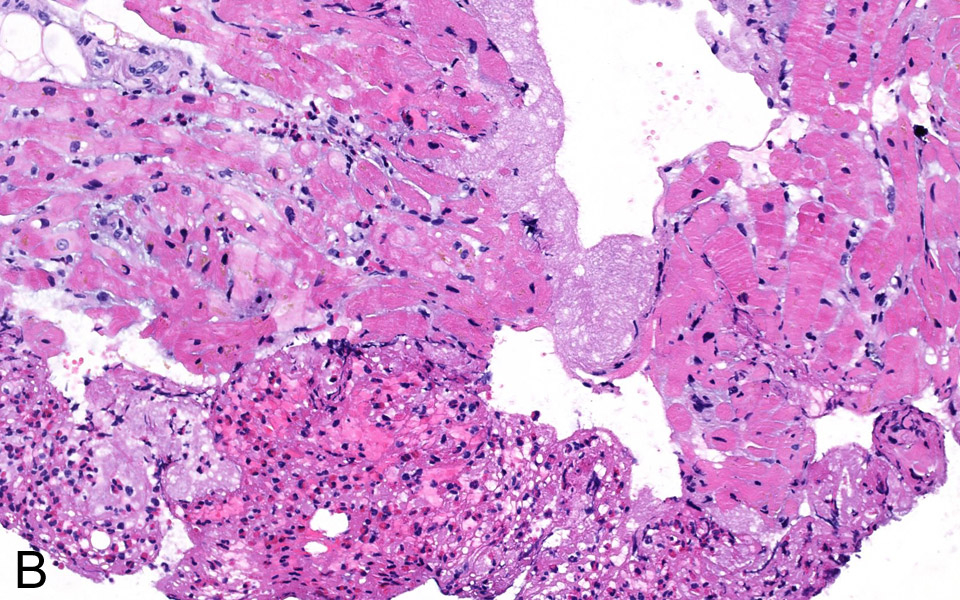

Figure 3B

Fibrinous thrombotic material mixed with numerous eosinophils was attached To the endocardium (H&E stain, 200x).

A 76-year-old woman was admitted for atypical chest pain and fatigue of 10 days’ duration. The clinical findings were irrelevant except for epigastric tenderness. The electrocardiogram (ECG) showed a borderline 0.1 mV horizontal ST depression in V4-V5 and minor ST abnormalities in V6, II, III and aVF leads (fig. 1). The chest radiography was normal. Blood analysis disclosed pathological levels of troponin-I (6.1ug/L; normal <0.30), total creatine phosphokinase (424 U/L; normal <167), creatine phosphokinase MB isoenzyme (84.1 µg/L, normal <3.4) and lactate dehydrogenase (243 U/L, normal <232). The leukocyte count was elevated (16.7 G/L, normal 4.0–10.0). Transthoracic echocardiography (TTE) showed a hyperkinetic left ventricle with a thickened interventricular septum and minimal pericardial effusion. Non-ST segment elevation myocardial infarction was diagnosed on the basis of the association of chest pain and a further increase of troponin-I (peak value 13.7 µg/L). The emergency angiogram showed normal coronary arteries. In the meantime, haematological study revealed persistent leucocytosis (peak value 19.9 G/L) with 67% eosinophilia, corresponding to an eosinophilic count of 13.2 G/L, elevation of eosinophil cationic protein (ECP; >200 µg/L, normal <16.0), IgE (685 kU/L, normal <100) as well as serum tryptase (12.2 µg/L, normal 1.0–11.4). Cardiac magnetic resonance (CMR) was performed on a Siemens Avanto 1.5T (Siemens Medical, Erlangen, Germany). The cine and delayed enhancement images (DE-CMR) revealed only aspecific hypocaptation in the infero-basal portion of left ventricular myocardium, without late enhancement (fig. 2). As further workup we performed a myocardial biopsy demonstrating an important sub-endocardial eosinophilic infiltrate with fibrin deposition and focal extension into the myocardium (fig. 3 A, B). Numerous intra- and perivascular eosinophils were also present in the interstitium. An extended aetiological workup was performed. The patient had a history of recurrent sinusitis and allergy to pollen and asthma. A solid neoplastic process was ruled out by thoraco-abdominal CT scan. Screening for parasites in the serum and stools was negative, as were serological tests for antibodies to viruses and biopsy for a myocardial infection. Haematological screening showed normal beta2-microglobulin and vitamin B12, no FIP1L1-PDGFRA mutation and normal immunoelectrophoresis. The immunological workup for vasculitis (ANCA, antimyeloperoxydase and anti-proteinase 3) was negative. On the basis of asthma, recurrent sinusitis, hypereosinophilia and the results of the heart biopsy, Churg-Strauss syndrome was diagnosed (table 1). Pulse endovenous corticosteroid treatment (500 mg i.v. prednisolone) was started just after the cardiac biopsy. At day 1 levels of blood eosinophils dropped to 0.4 G/L and the ECP level returned to normal values. The hospital course was uneventful and 3 months later the patient was still asymptomatic with a normal eosinophil count on oral prednisone.

Cardiac involvement is one of the more serious manifestations of CSS [6, 7] and hypereosinophilic syndromes (HES) [8, 9], accounting for approximately one-half of deaths attributable to CSS (table 1). The eosinophil-mediated heart damage evolves through three stages: acute necrotic, intermediate thrombotic and fibrotic stage. The first corresponds to our case and is usually clinically silent.